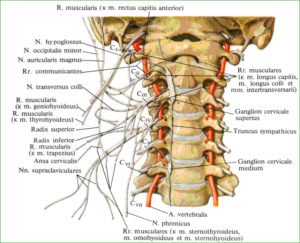

Шейная | Начало позвоночного столба, его верхняя часть, которая имеет выпукло-изогнутую форму и является самой подвижной зоной из пяти. Благодаря этому существует возможность наклона головы, поворотов и движений шеи. Состоит из семи позвонковых фрагментов, последний из которых считается пограничным и позволяет шейной зоне перейти в грудную. Позвонкам шейной зоны присвоено буквенное обозначение С и нумерация от 1 до 7. Первый представляет собой две дуги и служит опорой для черепа. Следующий тоже имеет нетипичное строение – спереди расположена ость, которая помогает вращаться первому позвонку. Отличается строением и седьмой, он является видоизмененным и служит проводником поперечной вены. Вся данная зона максимально близко расположена к мозгу, поэтому любые ее повреждения могут стать причиной летального исхода. |